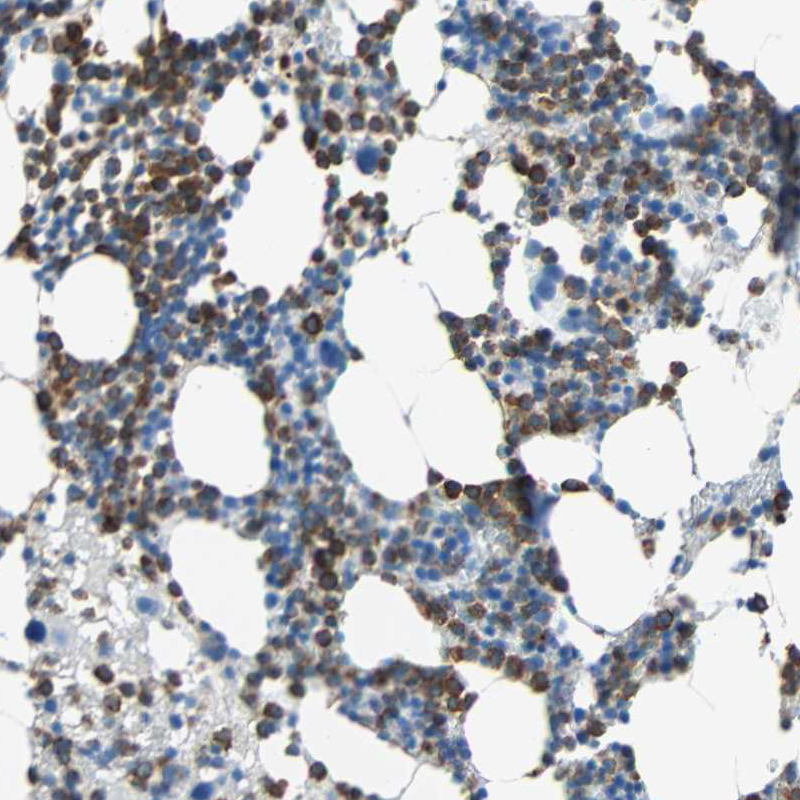

Immunohistochemical staining of human bone marrow shows membranous positivity in hematopoietic cells.